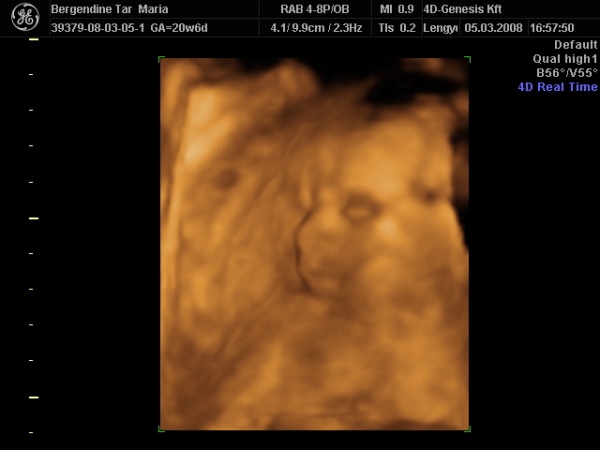

Szerencsére nálunk minden ok.,bár az AFP-től és a gen. UH-tól nagyon féltem, de szerencsére a múlt héten mindkettőt lezavartuk,és végre azt is megtudtuk, hogy Gréti babánk lesz.

Elvileg jövő héten megyünk 4D-re, teszek majd fel képeket.

Én azon lepődtem meg, hogy már nem igazán tudjuk egészben látni a törpéket, mert nem férnek rá a monitorra

Nem mintha nem lenne tök klassz, hogy már ilyen nagyok!